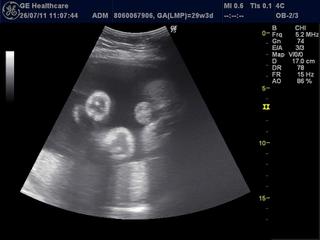

ahojte baby, tak som bola u doktora, musím ležať, nenamáhať sa, krčok má už len 2,62 cm, čo nie je dobré, ale ani až tak zlé, dobré je, že sa neotváram, plodová voda drží, tak len dúfať, že malinký počká ešte pár tt. a všetko dobre dopadne, ja tomu veľmi verím, si ale neviem predstaviť, že ja s mojou povahou byť v kľude....no bude to ťažké......dnes mi prišiel aj baldachýn na postieľku z ebay Trenčín, slabunko modrý, nádherný, neviem sa dočkať, kedy ju poskladáme a celú vyzdobíme, potom hodím aj pár foto 🙂